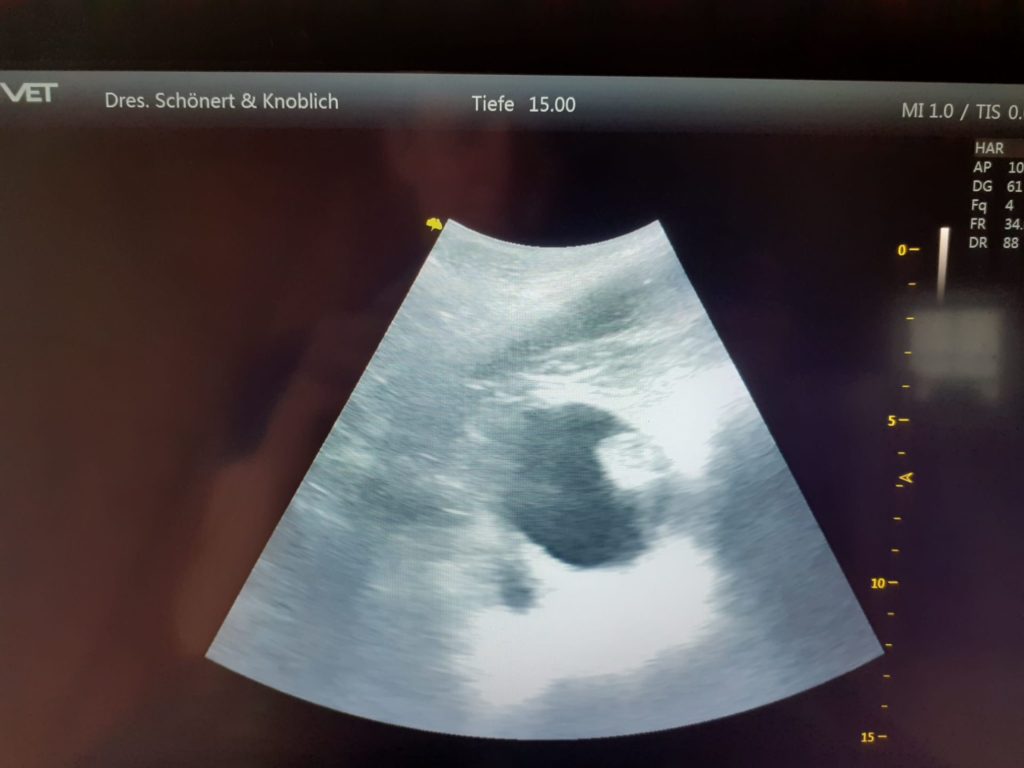

Das Ergebnis nach 100 Tagen, wir freuen uns auf das Fohlen im Mai 2025